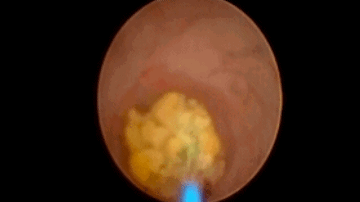

5.微创经皮肾镜取石,输尿管镜钬激光碎石术等。